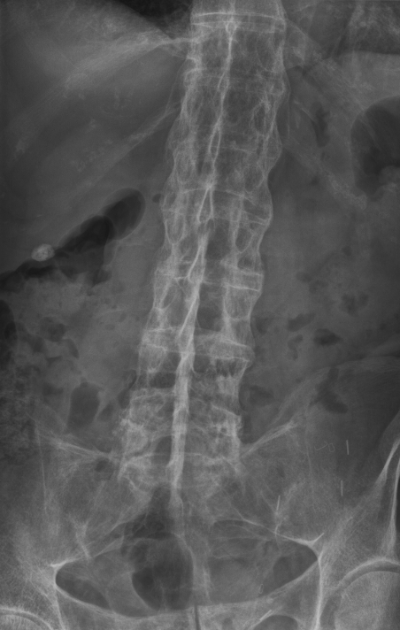

A 33-year-old man comes to the clinic because of years of gradually increasing lower back pain and morning stiffness. The pain radiates to the right groin and has been present for several years. Review of systems reveals episodic blurry vision and photophobia. Physical examination shows mild tenderness at the insertion of the Achilles tendon. A lumbar x-ray is obtained and is shown.

The human leukocyte antigen marker commonly associated with this man’s disease is also associated with which of the following disorders?

C) Psoriatic arthritis